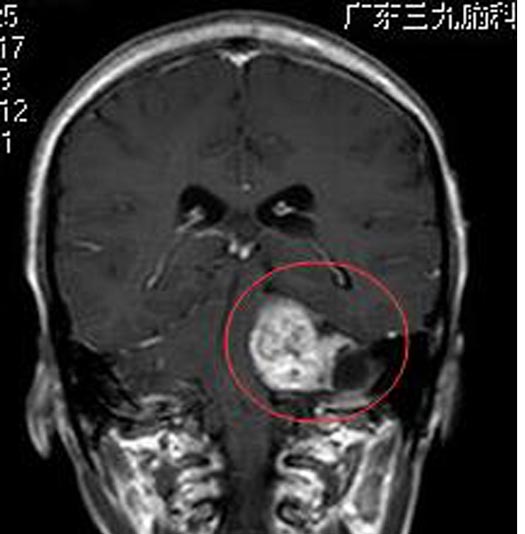

广东三九脑科医院进一步行头颅MR检查显示:左侧桥小脑角区可见一团块状囊实性占位性病变,大小约4.2cm×3.1cm×3.5cm,脑干及左侧桥壁、左侧小脑半球受压变形,四脑室受压变窄,考虑听神经瘤可能性大。